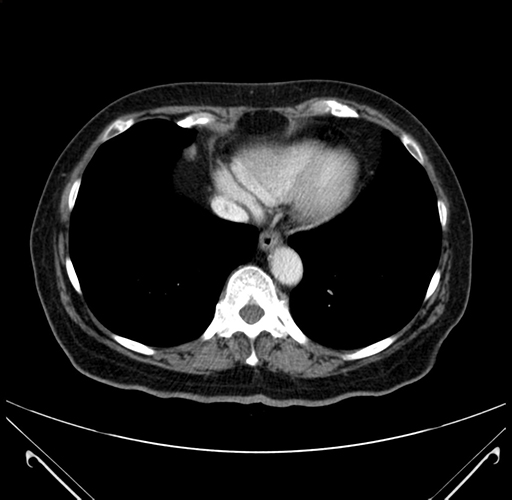

Pre-Chemo: Coronal Venous

Coronal Venous